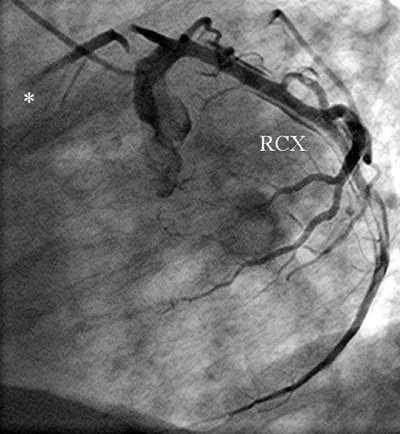

A 56-year-old obese man with a history of hypertension was admitted at night to the department of cardiology of our hospital because he had developed sudden onset right-sided thoracic pain with radiation into the right shoulder and right arm. He was sweating profusely and had massive nausea. The initially performed 12-lead ECG showed marked inferior ST segment elevations (Figure 1). Beside analgetics and oxygen, he was treated with aspirin, clopidogrel, heparin and the fibrin-specific thrombolytic tenecteplase. His symptoms resolved after 30 minutes. However, half an hour later, he developed left-sided thoracic pain, tachycardia, low blood pressure and the ECG signs of anterior ST-segment elevation myocardial infarction. The performed coronary angiography revealed a normal right coronary artery (Figure 2). The left coronary artery showed a long dissection of a large ramus circumflexus (RCX) (Figures 3,4). Additionally, the left anterior descending coronary artery (LAD) was occluded at about the mid-level (Figure 4, asterisk). Afterwards the left ventriculography revealed a reduced function and a Stanford type A aortic dissection with the intimal flap (Figure 5, arrows). Immediate patient transfer for emergency surgical intervention was arranged. During transport, ventricular fibrillation occurred, and he required endotracheal intubation as well as prolonged cardiopulmonary resuscitation. Unfortunately, he died due to a refractory cardiogenic shock during further transport.

Figure 4: The left coronary artery shows an occlusion of the left anterior descending coronary artery (*) (left anterior oblique projection, RCX: ramus circumflexus).